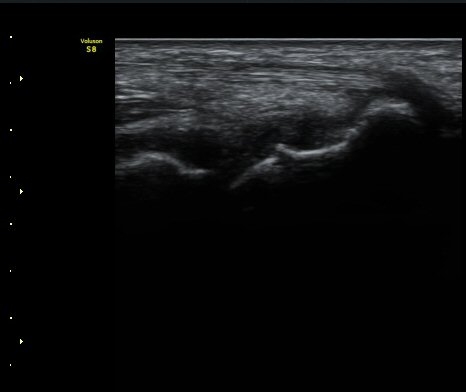

ÃÊÀ½ÆÄ °Ë»ç

¼Õ¸ñÀÇ Á¾´Ü

ÁÖ»ó°ñ ¼±»ó°ñÀýÀº ´Ü¼ø¹æ»ç¼± ÃÔ¿µ ½Ã È®ÀεÇÁö ¾ÊÀº °æ¿ì°¡ ¸¹Àºµ¥ ÀÌ ¶§ ÃÊÀ½ÆÄ

°Ë»ç°¡ ÁÖ»ó°ñ °ñÀý Áø´Ü¿¡ ¸Å¿ì À¯¿ëÇÏ´Ù. ±×·¯¹Ç·Î ¼Õ¸ñ ´ÙÄ£ ÈÄ Áö¼ÓÀûÀÎ ÅëÁõÀ»

È£¼ÒÇϰí ÁÖ»ó°ñ ºÎÀ§ ¾ÐÅëÀ» º¸ÀÌ´Â °æ¿ì ÃÊÀ½ÆÄ°Ë»ç¸¦ ½ÃÇàÇÏ¿© ÁÖ»ó°ñ °ñÀý ¿©ºÎ¸¦

È®ÀÎÇØ¾ß ÇÑ´Ù.